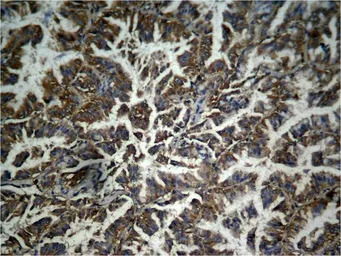

IHC-P analysis of human lung carcinoma tissue using GTX50727 beta Catenin (phospho Tyr333) antibody.